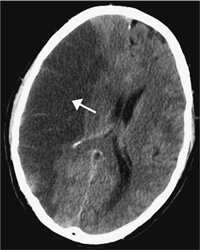

Иллюстрация к книге — Думай как математик. Как решать любые задачи быстрее и эффективнее [_52.jpg]

Стрелка на этом снимке, полученном с помощью метода компьютерной томографии, указывает на затененный участок мозга, поврежденный в результате инсульта правого полушария.